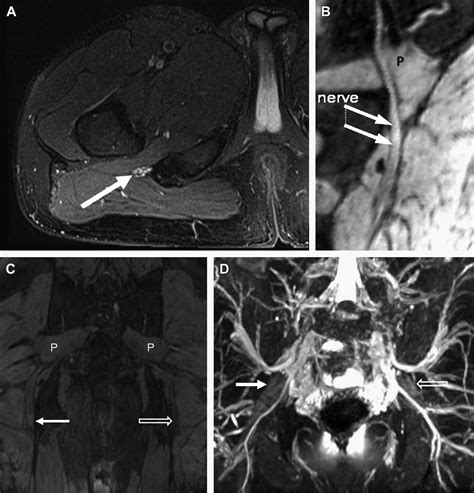

To overcome this, this specialized imaging employs specific pulse sequences designed to suppress the signal from fat—which often obscures nerve detail—while enhancing the signal from water-rich tissues like nerves. This process effectively makes the nerves "light up" on the resulting images, allowing radiologists to assess their anatomy, signal intensity, and trajectory in high detail.

• Nerve Entrapment Syndromes: Such as carpal tunnel syndrome, cubital tunnel syndrome, or tarsal tunnel syndrome.

• Sciatica and Radiculopathy: Identifying nerve root compression caused by herniated discs or other structural anomalies.

Once the images are acquired, they are analyzed by a radiologist with specialized expertise in musculoskeletal or neuroradiology. The goal is to identify changes in the nerve's appearance. For instance, a healthy nerve typically appears as a thin, uniform structure with a consistent signal. In contrast, an injured or compressed nerve may exhibit:

• Increased signal intensity: Often indicative of edema (swelling) or inflammation within the nerve.

• Nerve enlargement (fascicular thickening): A sign that the nerve is being subjected to chronic pressure or trauma.

• Discontinuity or disruption: Clearly visible in cases of severe trauma or nerve rupture.

• Masses or Lesions: Clear identification of tumor growth within or adjacent to the nerve sheath.